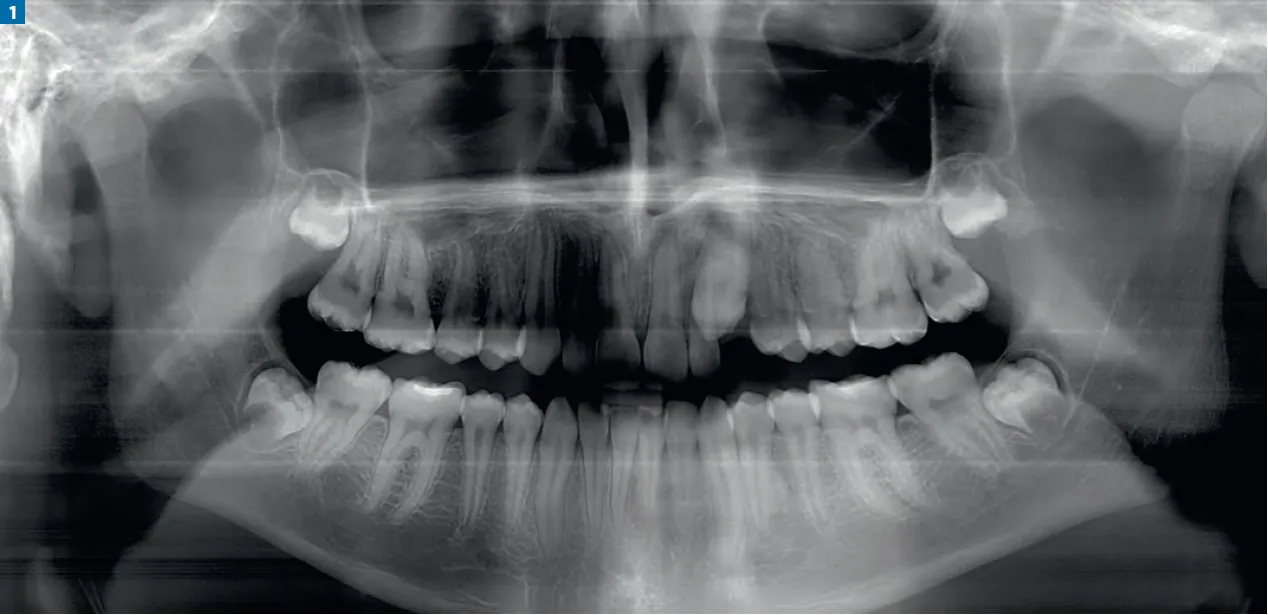

Zacznijmy od podstaw: „zęby oczne” to nic innego jak kły. W nomenklaturze stomatologicznej są to zęby oznaczone numerem 3 w każdym z czterech kwadrantów jamy ustnej. W uzębieniu mlecznym znajdziemy je pod numerami 53, 63, 73, 83, natomiast w uzębieniu stałym są to 13, 23, 33, 43. Ich rola jest absolutnie kluczowa dla prawidłowego funkcjonowania całego układu stomatognatycznego.

Kły są łatwe do zlokalizowania w jamie ustnej dzięki swojemu charakterystycznemu położeniu i kształtowi. Znajdują się one pomiędzy siekaczami (jedynkami i dwójkami) a zębami przedtrzonowymi (czwórkami i piątkami). Ich spiczasty, stożkowaty kształt jest nie do pomylenia z płaskimi siekaczami czy bardziej masywnymi przedtrzonowcami i trzonowcami. To właśnie ten kształt sprawia, że są one doskonale przystosowane do rozrywania pokarmu, pełniąc ważną funkcję w procesie żucia.

Tak, kły towarzyszą nam przez całe życie, choć w dwóch "edycjach". Posiadamy zarówno kły mleczne, jak i stałe. Kły mleczne są częścią pierwszego uzębienia dziecka i, podobnie jak inne mleczaki, wypadają, ustępując miejsca zębom stałym. Z mojego doświadczenia wynika, że ich wyrzynanie to często jeden z trudniejszych etapów ząbkowania. Kły mleczne zazwyczaj pojawiają się między 16. a 23. miesiącem życia dziecka. Kły stałe natomiast wyrzynają się znacznie później, zazwyczaj między 9. a 13. rokiem życia, zastępując swoich mlecznych poprzedników.

Po okresie ząbkowania mleczaków następuje czas na zęby stałe. Kły stałe zastępują kły mleczne zazwyczaj między 9. a 13. rokiem życia. Proces ten jest fascynujący: korzenie zębów mlecznych ulegają stopniowej resorpcji (rozpuszczaniu się), a pod nimi rozwijają się zawiązki zębów stałych, które powoli przesuwają się ku powierzchni dziąsła. W końcu ząb mleczny staje się na tyle rozchwiany, że wypada, ustępując miejsca nowemu, stałemu kłowi. To naturalny cykl, który świadczy o prawidłowym rozwoju uzębienia.Rola kłów w prawidłowym zgryzie i estetyce uśmiechu

Z mojego punktu widzenia, kły stałe odgrywają niezwykle ważną rolę w prawidłowym funkcjonowaniu jamy ustnej. Są one niczym filary, które stabilizują cały łuk zębowy. Ich obecność i odpowiednie ułożenie są kluczowe dla prawidłowego ustawienia pozostałych zębów, zapobiegając ich przemieszczaniu się. Kły stanowią również istotny element estetyki uśmiechu ich kształt i położenie wpływają na symetrię twarzy oraz prawidłowe rysy. Są one także odpowiedzialne za prowadzenie żuchwy podczas ruchów bocznych, chroniąc pozostałe zęby przed nadmiernym obciążeniem.

Niestety, zdarza się, że kły stałe, zwłaszcza górne, nie wyrzynają się prawidłowo i pozostają zatrzymane w kości. Oznacza to, że ząb nie jest w stanie samodzielnie przebić się przez dziąsło i zająć swoje miejsce w łuku zębowym. Z mojego doświadczenia wynika, że taka sytuacja wymaga interwencji ortodontycznej, a czasem również chirurgicznej. Ortodonta może zastosować aparaty, które pomogą ściągnąć zatrzymany kieł do prawidłowej pozycji. W niektórych przypadkach konieczne jest chirurgiczne odsłonięcie zęba, aby umożliwić jego prawidłowe wprowadzenie do łuku. Wczesna diagnoza jest tu kluczowa, dlatego regularne wizyty kontrolne u stomatologa i ortodonty są tak ważne.